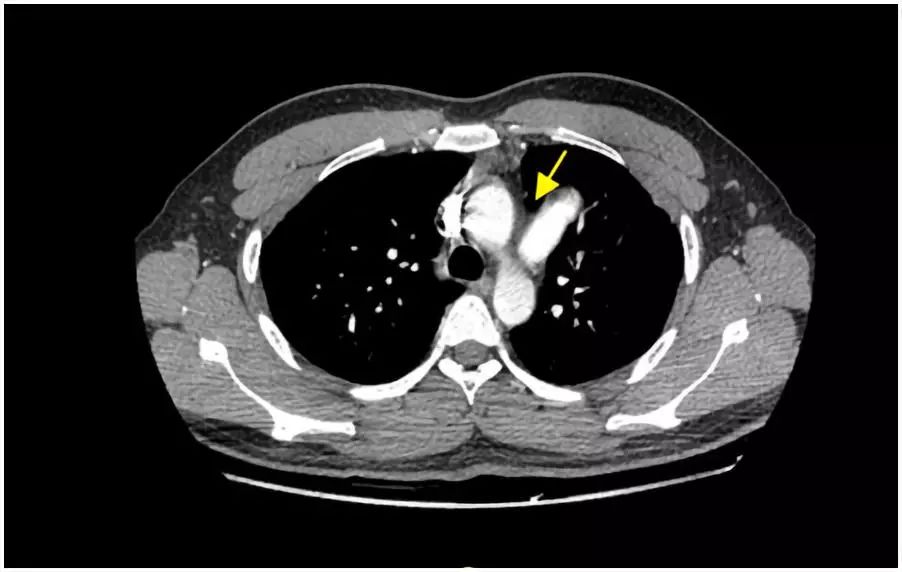

杜鑫主任仔细阅图后考虑该患者患有罕见的先天性心包缺如,建议行胸部CT检查。最终CT检查结果(图6、图7)证实了超声诊断。

图6. CT检查示主动脉和肺动脉之间有异常肺组织楔入,提示该处心包缺如